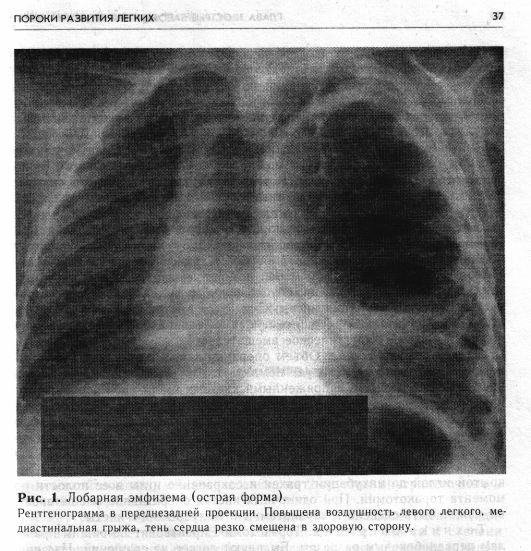

Решающее значение в постановке диагноза лобарной эмфиземы имеют данные рентгенологического исследования. На обзорной рентгенограмме грудной клетки видно, что пораженный отдел легкого увеличен, на повышенном воздушном фоне его — тени средне- и крупнокалиберных сосудистых разветвлений. Соседние участки легкого коллабирова-ны. Раздутая доля частично проникает в противоположную сторону грудной клетки, смещая средостение и образуя медиастинальную грыжу. При остром течении долевой эмфиземы проведение других дополнительных диагностических методов исследования часто невозможно, так как нарастающее ухудшение общего состояния ребенка требует немедленного оказания хирургической помощи.

Рентгенологически выявляется обширная воздушная полость, занимающая всю половину грудной клетки, легочный рисунок отсутствует,

тень сердца и органов средостения резко смещена в здоровую сторону. Имеются признаки медиастинальной грыжи (рис. 1).